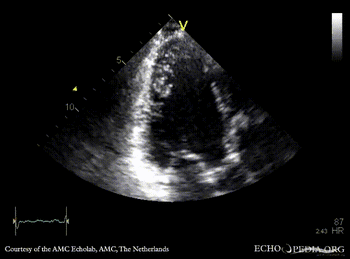

A4CH A4CH with Color Doppler: severe mitral valve regurgitation